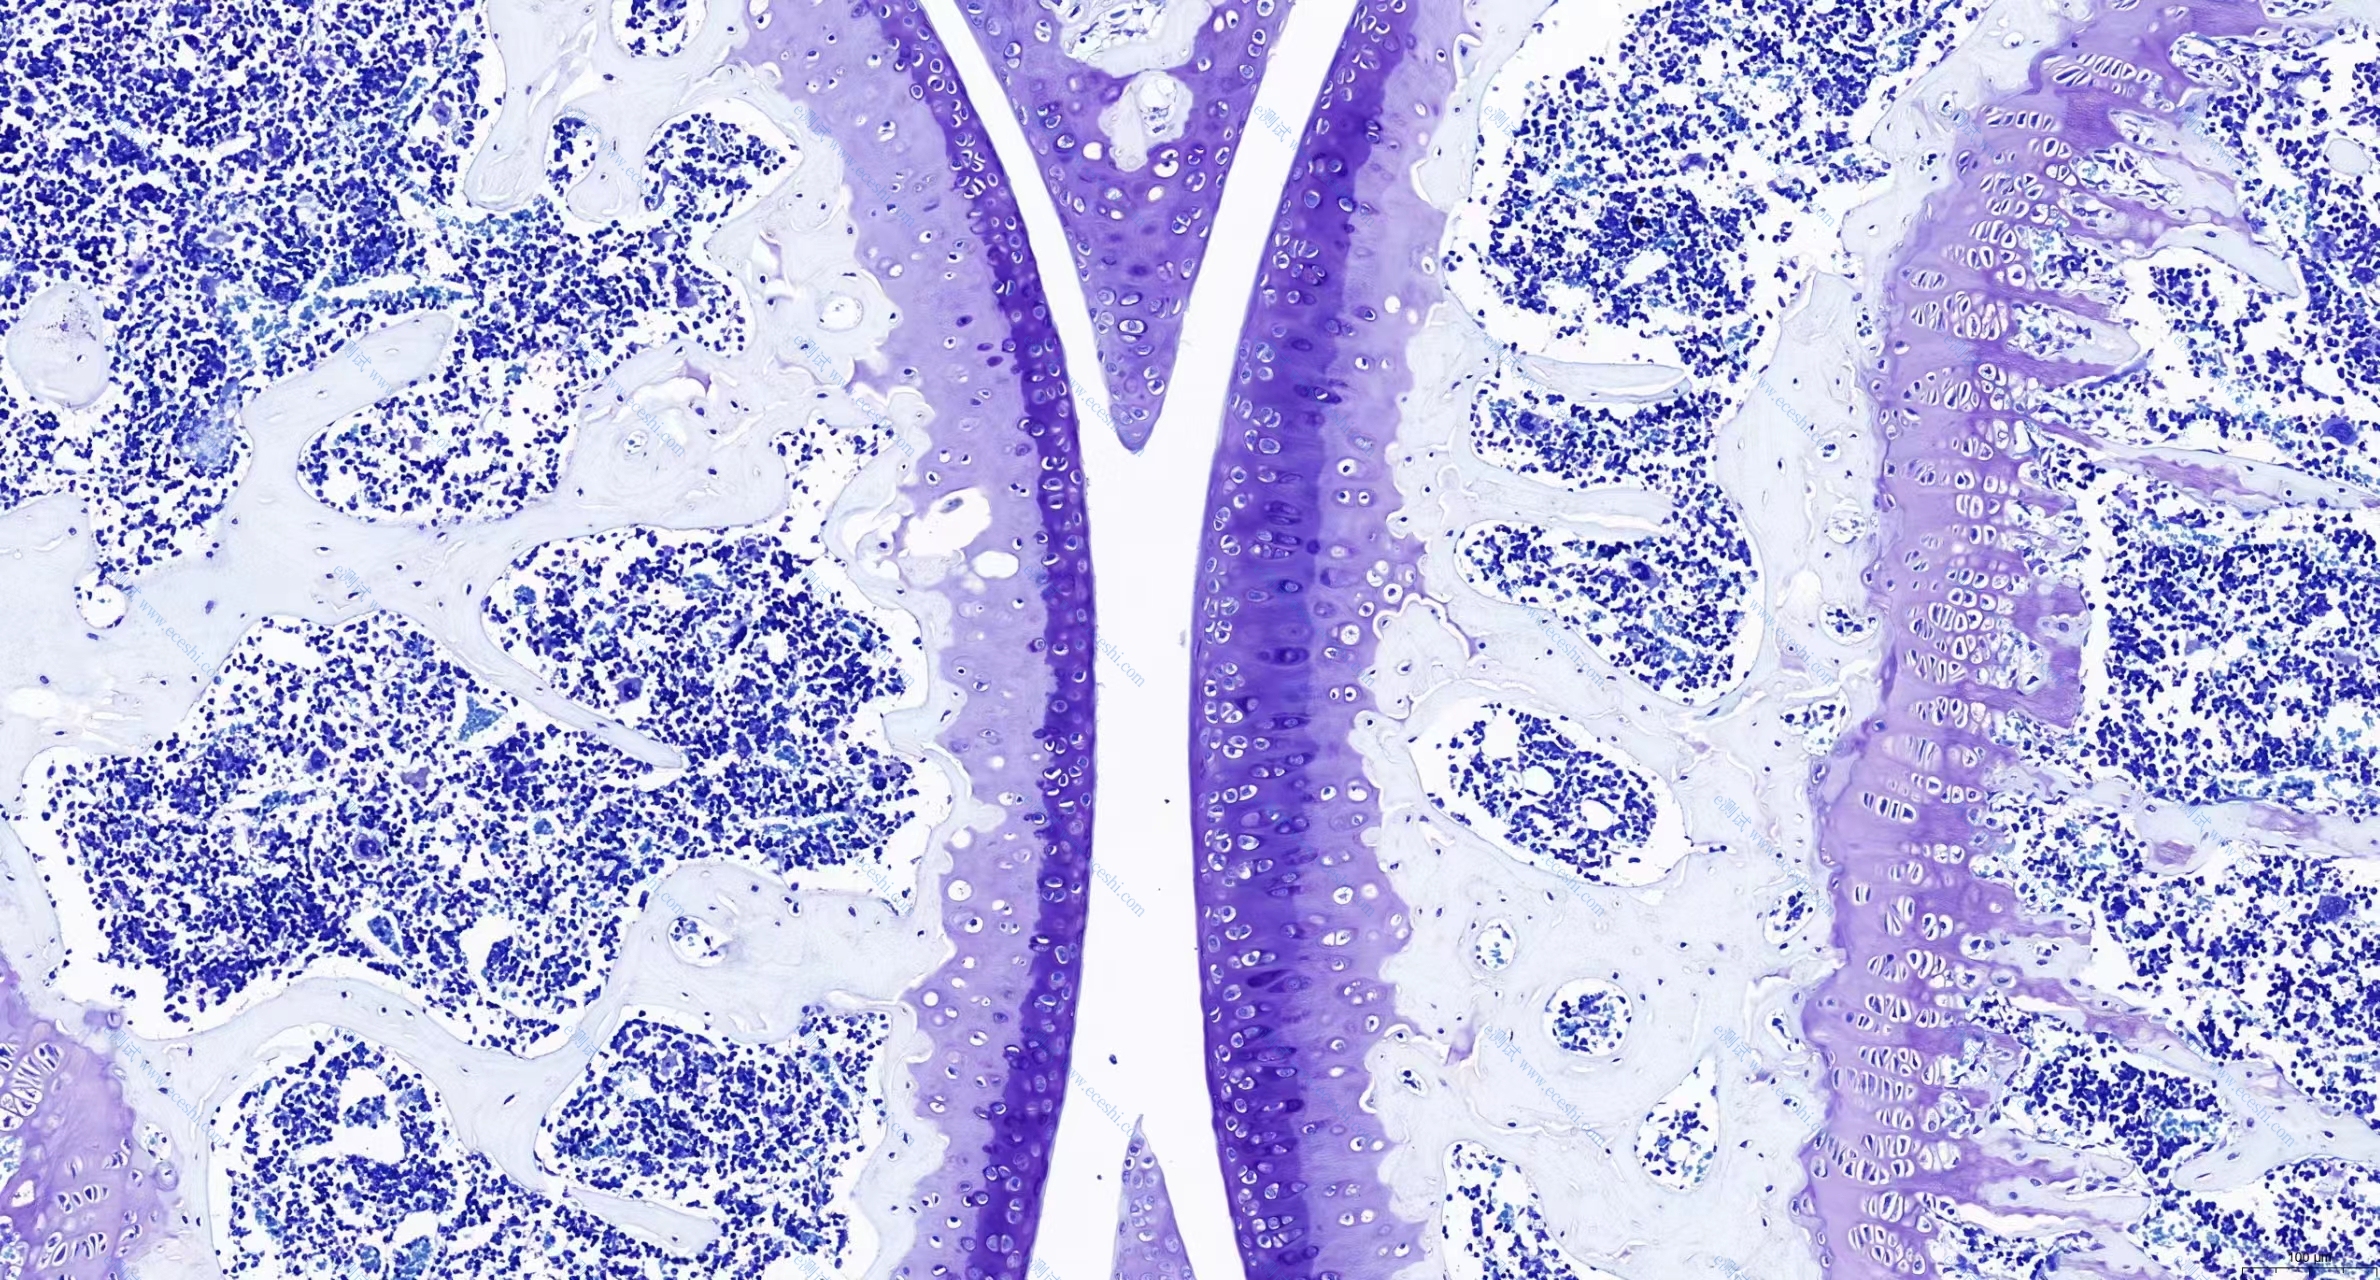

1、HE染色

3、甲苯安蓝染色